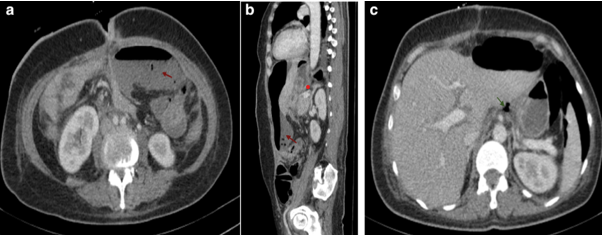

Kehr's Sign in Postoperative Digestive Surgery: A Radiological Red Flag for Pneumoperitoneum

Bouanane Rania, Taibi Ouiam, El Aouadi Salma, Retal Hamza, F.Z Laamrani, Youssef Omor, Rachida Latib and Sanae Amalik. 8(11): 01-04.